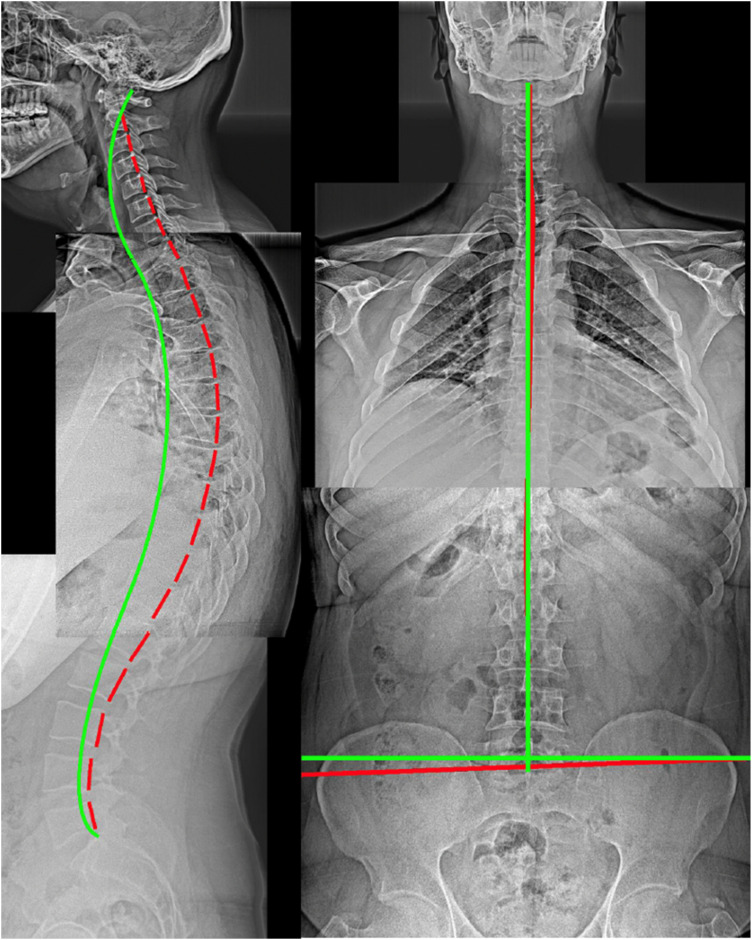

Postural alignment is a critical determinant of health status. Its degradation is associated with deformity-caused and compensation-related back pain, neurologic involvement, osteoarthritic development, as well as disability and reduced quality of life. Radiography remains the most efficient method of evaluating standard sagittal and coronal spine and pelvic metrics that are used to plan surgical and nonsurgical treatment strategies. Many current spine guidelines dissuade the use of initial screening X-rays and some chiropractic guidelines condemn repeat imaging to assess progress from treatment regimens; these are anti-scientific viewpoints that ignore alternate viewpoints and evidence. Current understanding of the relationship between different spinopelvic parameters are essential to plan biomechanically appropriate interventions that are patient-specific. There are radiographically measured parameter thresholds critically related to several spinal disorders and positive patient outcomes. Current guidelines must include a caveat for contemporary biomechanical evaluation and its consequent specific treatments and should recommend routine radiographic imaging for spine patients undergoing corrective rehabilitative interventions. The failure to radiographically diagnose spinal deformity is argued to be negligence in many cases. The prime obstacle to routine X-ray imaging lies with the presumed threat of cancer, however, this is dogma; we summarize the main evidence from recent publications why this is so.

Abstract Image